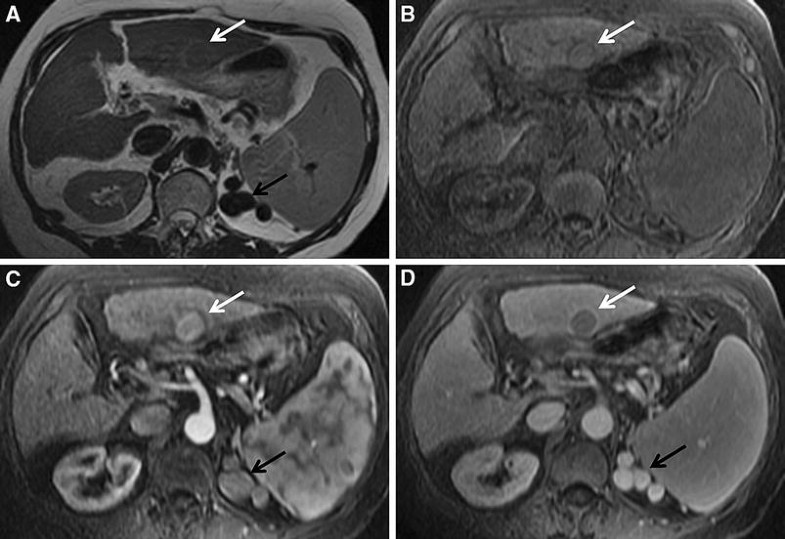

Autoimmune hepatitis in practice, from diagnosis to complications What Autoimmune Hepatitis Mri To exclude other possibilities of chronic hepatitis. Ct and mri scans can look at your liver in more detail. Depending on the degree of liver injury, lab values may indicate depressed liver function (e.g. Read more about scans and imaging tests here. How do doctors diagnose autoimmune hepatitis? Liver histology is mandatory for the diagnosis of autoimmune hepatitis. Assessing the. Autoimmune Hepatitis Mri.

Autoimmune hepatitis in practice, from diagnosis to complications What Autoimmune Hepatitis Mri To retrospectively evaluate the morphologic and enhancement features of the liver on magnetic. To exclude other possibilities of chronic hepatitis. Assessing the degree of inflammatory activity such as interface and lobular inflammation, which is not. Ct and mri scans can look at your liver in more detail. Read more about scans and imaging tests here. Depending on the degree of. Autoimmune Hepatitis Mri.

Autoimmune hepatitis in practice, from diagnosis to complications What